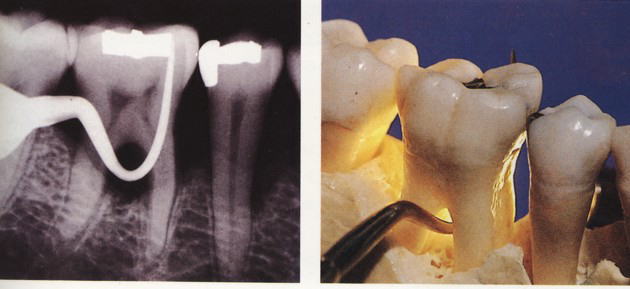

『ラ タイチャークの図版』より

根分岐部病変(こんぶんきぶびょうへん)は歯根が複数ある歯について、歯根の分かれ目(分岐部)を埋めていた歯槽骨が歯周病などの原因で溶けて失われ、周囲に炎症が生じている状態を言います。大臼歯、特に下顎の大臼歯に多く見られます。

根分岐部病変が一旦発症してしまうと、その治療はなかなか困難です。多くの場合大臼歯部で起こるため、その位置的な事情や歯根の懈怠の複雑さなどから、正確な診断、術者側の施術、患者さんの管理などいずれも困難を極めます。

治療法としては様態に応じて、スケーリング・ルートプレーニング・分岐部入り口の整形によって磨きやすい形態を作る→歯槽骨の整形→歯根に対する処置(いずれかの根を抜歯する・複数の根の間を分割するなど)やトンネルの形成などの処置があります。 また「再生療法」として薄い皮膜を用いて歯槽骨の再生を誘導する『組織再生誘導法(GTR法)』や特殊な薬剤を用いる『エムドゲイン法』などがあります。 |